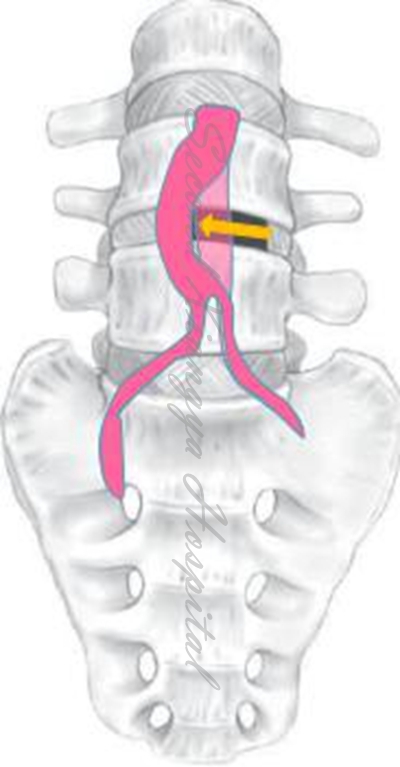

4.L4/5及以上节段,用常规腹部拉钩将将腹主动脉和静脉向内侧牵开,但不用过中线;

血管拉开示意图

5.另一拉钩置于椎体侧前、交感神经链前方,将其稍向后牵开;

拉钩示意图